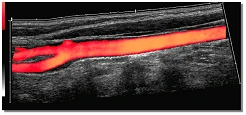

Mit dem Panorama-Bildverfahren können Sie bis zu 60 cm am Stück dargestellt werden. Jährlich werden hier 9.000 Patienten von den Fachärzten der Nuklearmedizinischen Klinik untersucht.